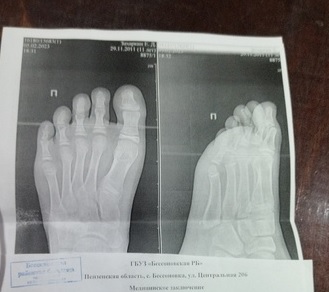

Автор сообщения приложила снимок, на котором видно сильное повреждение ноги – преодолеть четыре этажа ступеней с такой травмой действительно нелегко.